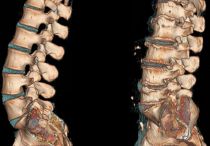

Основные техники массажа при грыже поясничного отдела позвоночника

Зачем нужен массаж при поясничной грыже: эффективность, показания к процедуре, общие правила массажа. Виды, техники выполнения, противопоказания.